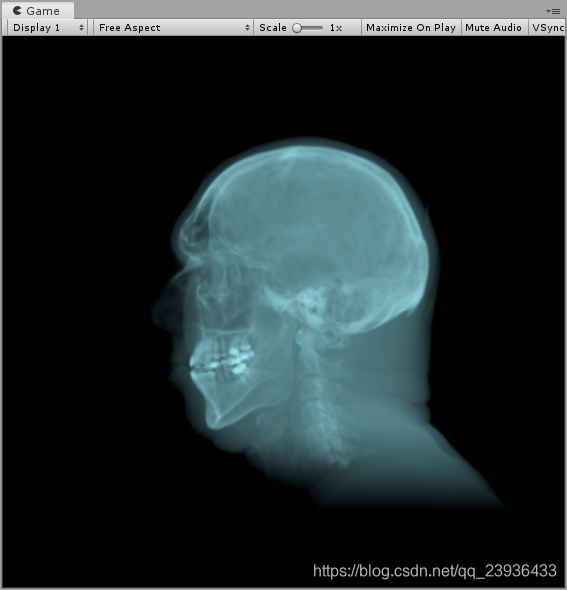

同理,如果我们想获得深层中的高密度的骨骼,我们就可以通过增大_Density值,同时增大_Contrast值使得密度差拉大,这样我们就可以显示出我们想要的高密度骨骼信息,

效果如下: